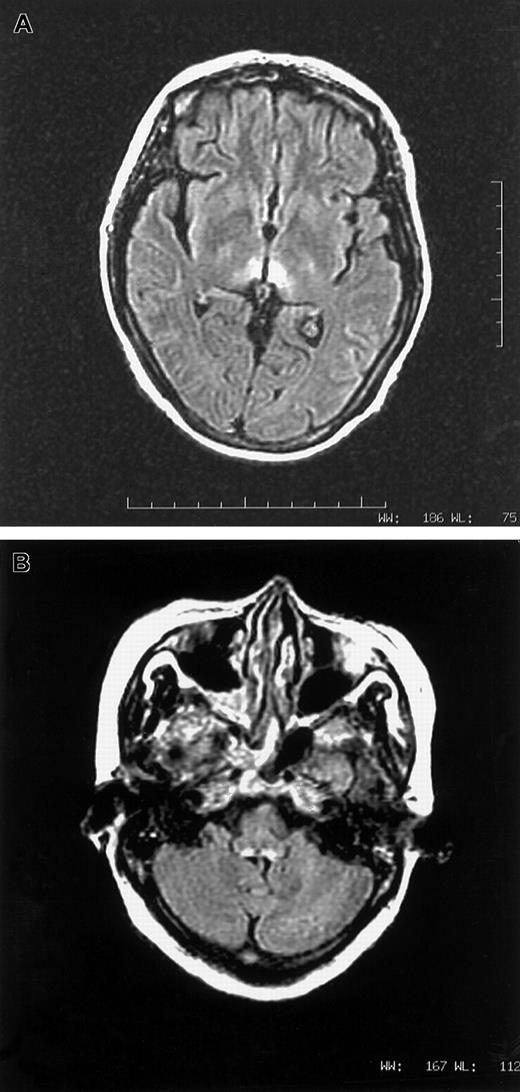

(A,B) MRI images in axial fluid attenuated inversion recovery sequence showing T2-weighted hyperintense lesions surrounding third ventricle (1A) and dorsal aspect of medulla (1B).

A vegetarian woman, aged 46, with relapsed APL, t(15:17), was given arsenic trioxide 10 mg/d for 28 days. Her first induction with all-trans retinoic acid and daunorubicin a year ago was uncomplicated. Medical history was unremarkable. In particular, there was no prior neurological disorder. Her diet was mainly refined rice and leafy vegetables, very sparse in meat and beans. Starting from day 17, she experienced nausea and vomiting. Pain and congestion were noted over the tongue, throat, and conjunctiva. On day 33, she complained of numbness over lower limbs. Confabulation was absent. On day 37, all 4 limbs were paralyzed and areflexic. Speech was inaudible and bulbar paralysis was noted. She sweated heavily and had a vesicular rash over her body. Cerebrospinal fluid showed white count, 1/μL; protein, 0.5 gm/L; and glucose, 6.7 mM. Studies for Venereal Disease Research Laboratory, bacteria, fungus, virus, and oligoclonal band were negative. Nerve conduction study detected generalized reduction of sensory action potential. Motor conduction was normal, while electromyogram showed active denervation. Drug review did not suggest a neurotoxic side effect from any supportive medication. With cranial magnetic resonance imaging (MRI), lesions consistent with Wernicke syndrome were seen over tectum, periaqueductal gray, and periventricular white matter of the third ventricle, both thalami, and the dorsal medulla (Figure1A,B). The low level of red cell (RBC) transketolase (24 μmol/min L; normal 45-90 μmol/min L), which increased by 32% after in vitro addition of thiamine pyrophosphate, confirmed thiamine deficiency. Parental thiamine 100 mg/d was given. The next day, power of the upper limbs dramatically improved and speech became audible. Over the next 5 days, upper limbs regained full power. As2O3 at 5 mg/d for 28 days as maintenance was given 5 weeks later, with oral thiamine. There was no deterioration in neurology. Lower limb power continuously improved. RBC transketolase during arsenic maintenance was normal, and MRI scan demonstrated complete resolution of all previous abnormalities.